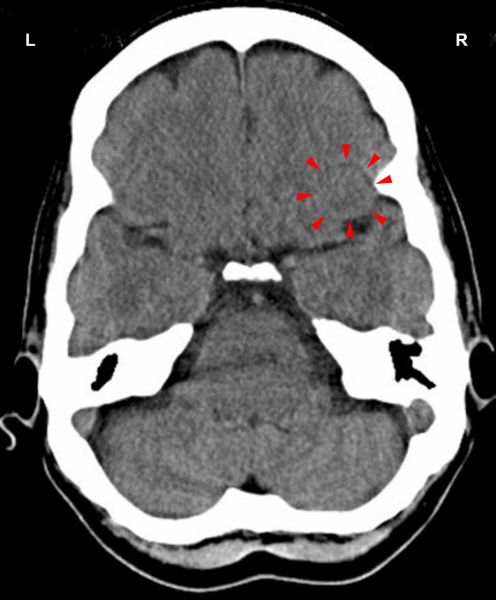

On this CT scan we see the impact of a stink conflict in the area of the sensory cortex that controls the nasal mucosa of the left half of the nasal cavity (view the GNM diagram). For a right-handed person the conflict is associated with his/her mother or child; for a left-hander with a partner. The uneven, partly edematous ring of the Hamer Focus reveals that the person has already resolved the conflict and is now in the healing phase with symptoms of a cold.